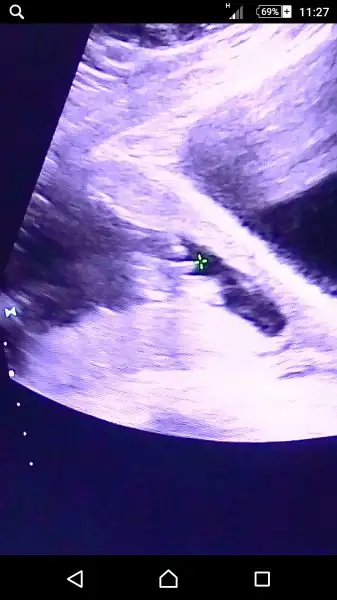

Ramzi Teorisi ve cinsiyet tahmini ( tutma olasılığı %85 miş )

Ramzi teorisine göre ( bilimsel bir araştırma sonucuymuş ve %85 doğruluğu varmış). İlk 6-8 haftalık ultrason görüntüsüne göre bebeğin kesenin içersinde soldan ya da sağdan girişine göre cinsiyet tahmini yapılıyor. Bilimsel olunca tecrübeli annelerimiz yada anne adaylarımızdan yardım istiyoruz. Doğruluğu var mı öğrenmek adına :) Bizleri aydınlatırsanız çok seviniriz. bu teorieye göre;

Yanlış hatırlamıyorsam ortaya yakin bi yerden baktı ama ben uzanınca benim sağıma yakindi.ama bebek ultrason fotosunda 7 haftalıkken solda kağıda bakınca,karnıma tutunca sagda bu teoriye gore benimki ne oluyor:)bu resme gore bana nerden bakmış

doktor veya sen değil canım. ultrason kağıdına bak. düz mantık direk. bakarken keseye soldan girmişse erkek, sağdan girmişse kız. karından muayeneye göre.

çok teşekkürler. bu teoriye göre tutmuş belliki :) . Benim kesemde aynı böyleydi ilk zamanlar ne biçimsiz demiştim. hayırlı olsun sanada :) belirtilerin vs neydi mide bulantın oldumu hiç

Kız ben onu anlamadım iste keseye sağdan mi soldan mi girdi:)benim resimleri biliyon cnm bi bak:)